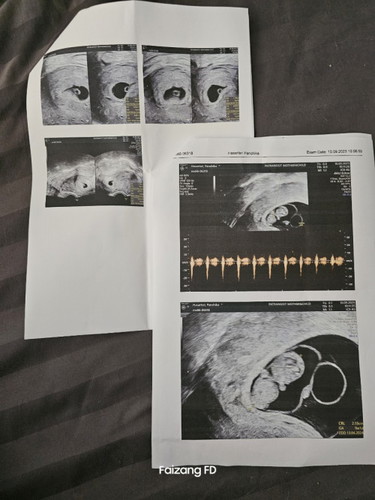

ในแอป 10 w แต่ซาว์ด 9+1 w

จากเดือนที่แล้วที่หมอบอกผนังมดลูกหนามาก มาเดือนนี้เปลี่ยนคุณหมอ ได้เห็นตัวเล็กนอน กระดิกขา หัวใจเต้น 120 ต่อนาที น้ำตาจะไหล ดีใจที่มีพัฒนาการ และหมอแจ้งผนังมดลูกปกติ ไม่ได้หนาเกินไปเลย แต่งงตรง หารอบที่แล้วอายุครรภ์ตรงกับแอป แต่รอบนี้ไม่ตรง เคลื่อนไปประมาณ 5 วัน หรือเรากินไม่ลงน้องค่ะ ต้องบำรุงอะไรเพิ่มไหม

กำลังจะมีลูก